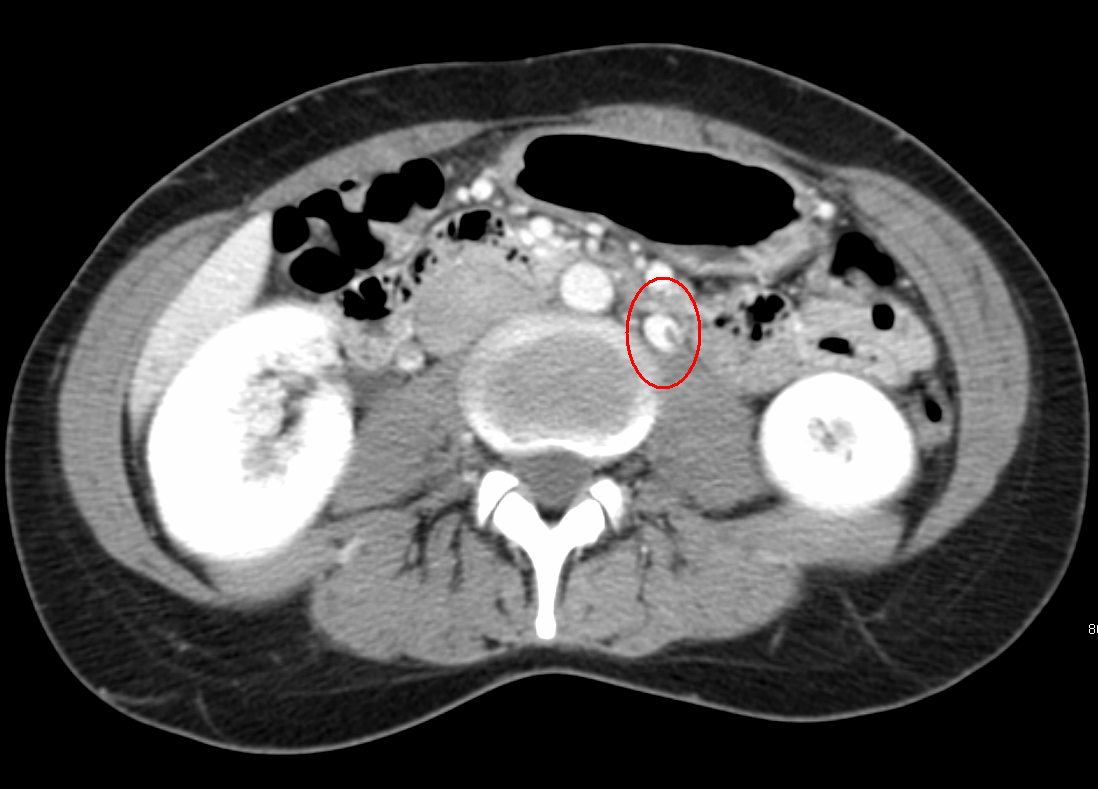

From radiopaedia.org

Nutcracker syndrome (annotated CT) Image Nutcracker Syndrome Embolization The most common sign and symptom associated with ncs are hematuria and left flank pain, respectively. Anatomic compression of the left renal vein in the angle between the aorta and superior mesenteric artery may be asymptomatic or may result in symptoms, including. Nutcracker syndrome is a rare condition that can be successfully treated with renal vein stenting via an endovascular.. Nutcracker Syndrome Embolization.